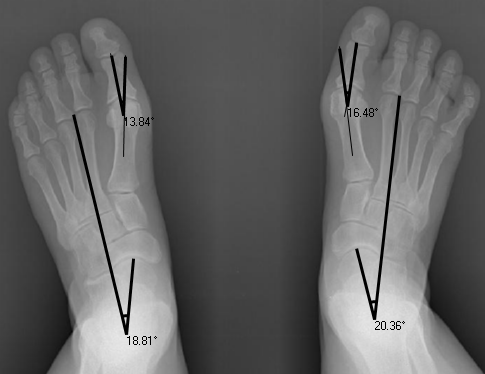

Following our initial assessment, which included an x-ray, we prescribed a course of foot mobilisation therapy in conjunction with strengthening exercises.

On measuring the difference between the angles of deviation before and after treatment, our foot specialist found that Jennifer's bunions had reduced significantly with an 8 degree change in her right big toe and 4 degrees on the left. An ideal reading is between 12-15 degrees.The great news is that with minimal ongoing podiatry treatment, we will be able to further straighten the bunion until there is no deviation whatsoever. The magnitude of improvement only took three months, and the best is yet to come.